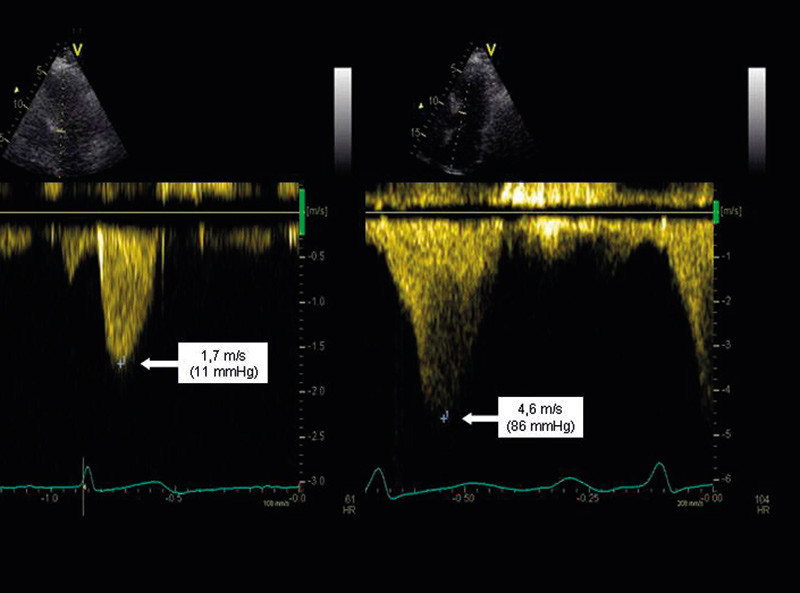

Patients suffering from hypertrophic cardiomyopathy (HCM) often have dyspnoea and reduced capacity to work as their main symptoms. These are not very specific, and may be caused by systolic as well as diastolic dysfunction. In addition, this condition may occur both with and without any obstruction of the left ventricle outflow tract. Ergometric stress echocardiography is well suited for an examination of this condition. It has been shown that more than one-third of all patients with hypertrophic cardiomyopathy without any obstruction of outflow at rest may have a significant obstruction under stress (1). The obstruction increases the pressure drop in the left outflow tract, and it is assumed that a maximum pressure drop of > 30 mmHg and/or a stress-induced pressure drop of > 50 mmHg are of clinical significance. These values are used as a threshold for treatment with alcohol ablation or myectomy (2).

The pressure drop is calculated from bloodstream velocities measured by continuous Doppler from the apex of the heart by the simplified Bernoulli equation ΔP = 4v2 (where ΔP is the pressure drop measured in mmHg and v is the maximum blood-flow velocity measured in m/s) (3).

The obstruction of the outflow tract may cause the anterior leaflet of the mitral valve to be drawn forward during the systole and causes the so-called SAM (systolic anterior movement) phenomenon. This could result in an obstruction of the outflow tract, and a significant mitral insufficiency may occur. The blood flow from this mitral insufficiency may be located close to the blood flow in the outflow tract, so that distinguishing between them may be difficult. Often, parts of both velocity signals are included in the same registration. However, they can be distinguished by the fact that the blood flow in the mitral insufficiency starts earlier than the blood flow through the outflow tract, and because the obstruction produces a late-systolic, powerful acceleration of the blood-flow velocity, with a characteristic, knife-shaped signal (Figure 2).

Figure 2.  A patient with hypertrophic obstructive cardiomyopathy. Echocardiography with continuous Doppler registration of…

Figure 2. A patient with hypertrophic obstructive cardiomyopathy. Echocardiography with continuous Doppler registration of the outflow from the left ventricle. Recording at rest (left) and during exercise with a supine bicycle (80 W) (right). The two images have different scales for time and velocity. The figure shows the maximum blood-flow velocity and estimated pressure drop in the outflow from the left ventricle (the pressure drop is equal to the square of the velocity multiplied by 4). The estimated pressure drop increased from 11 mmHg at rest to 86 mmHg during physical exercise, which is consistent with a stress-induced increase in the outflow obstruction.